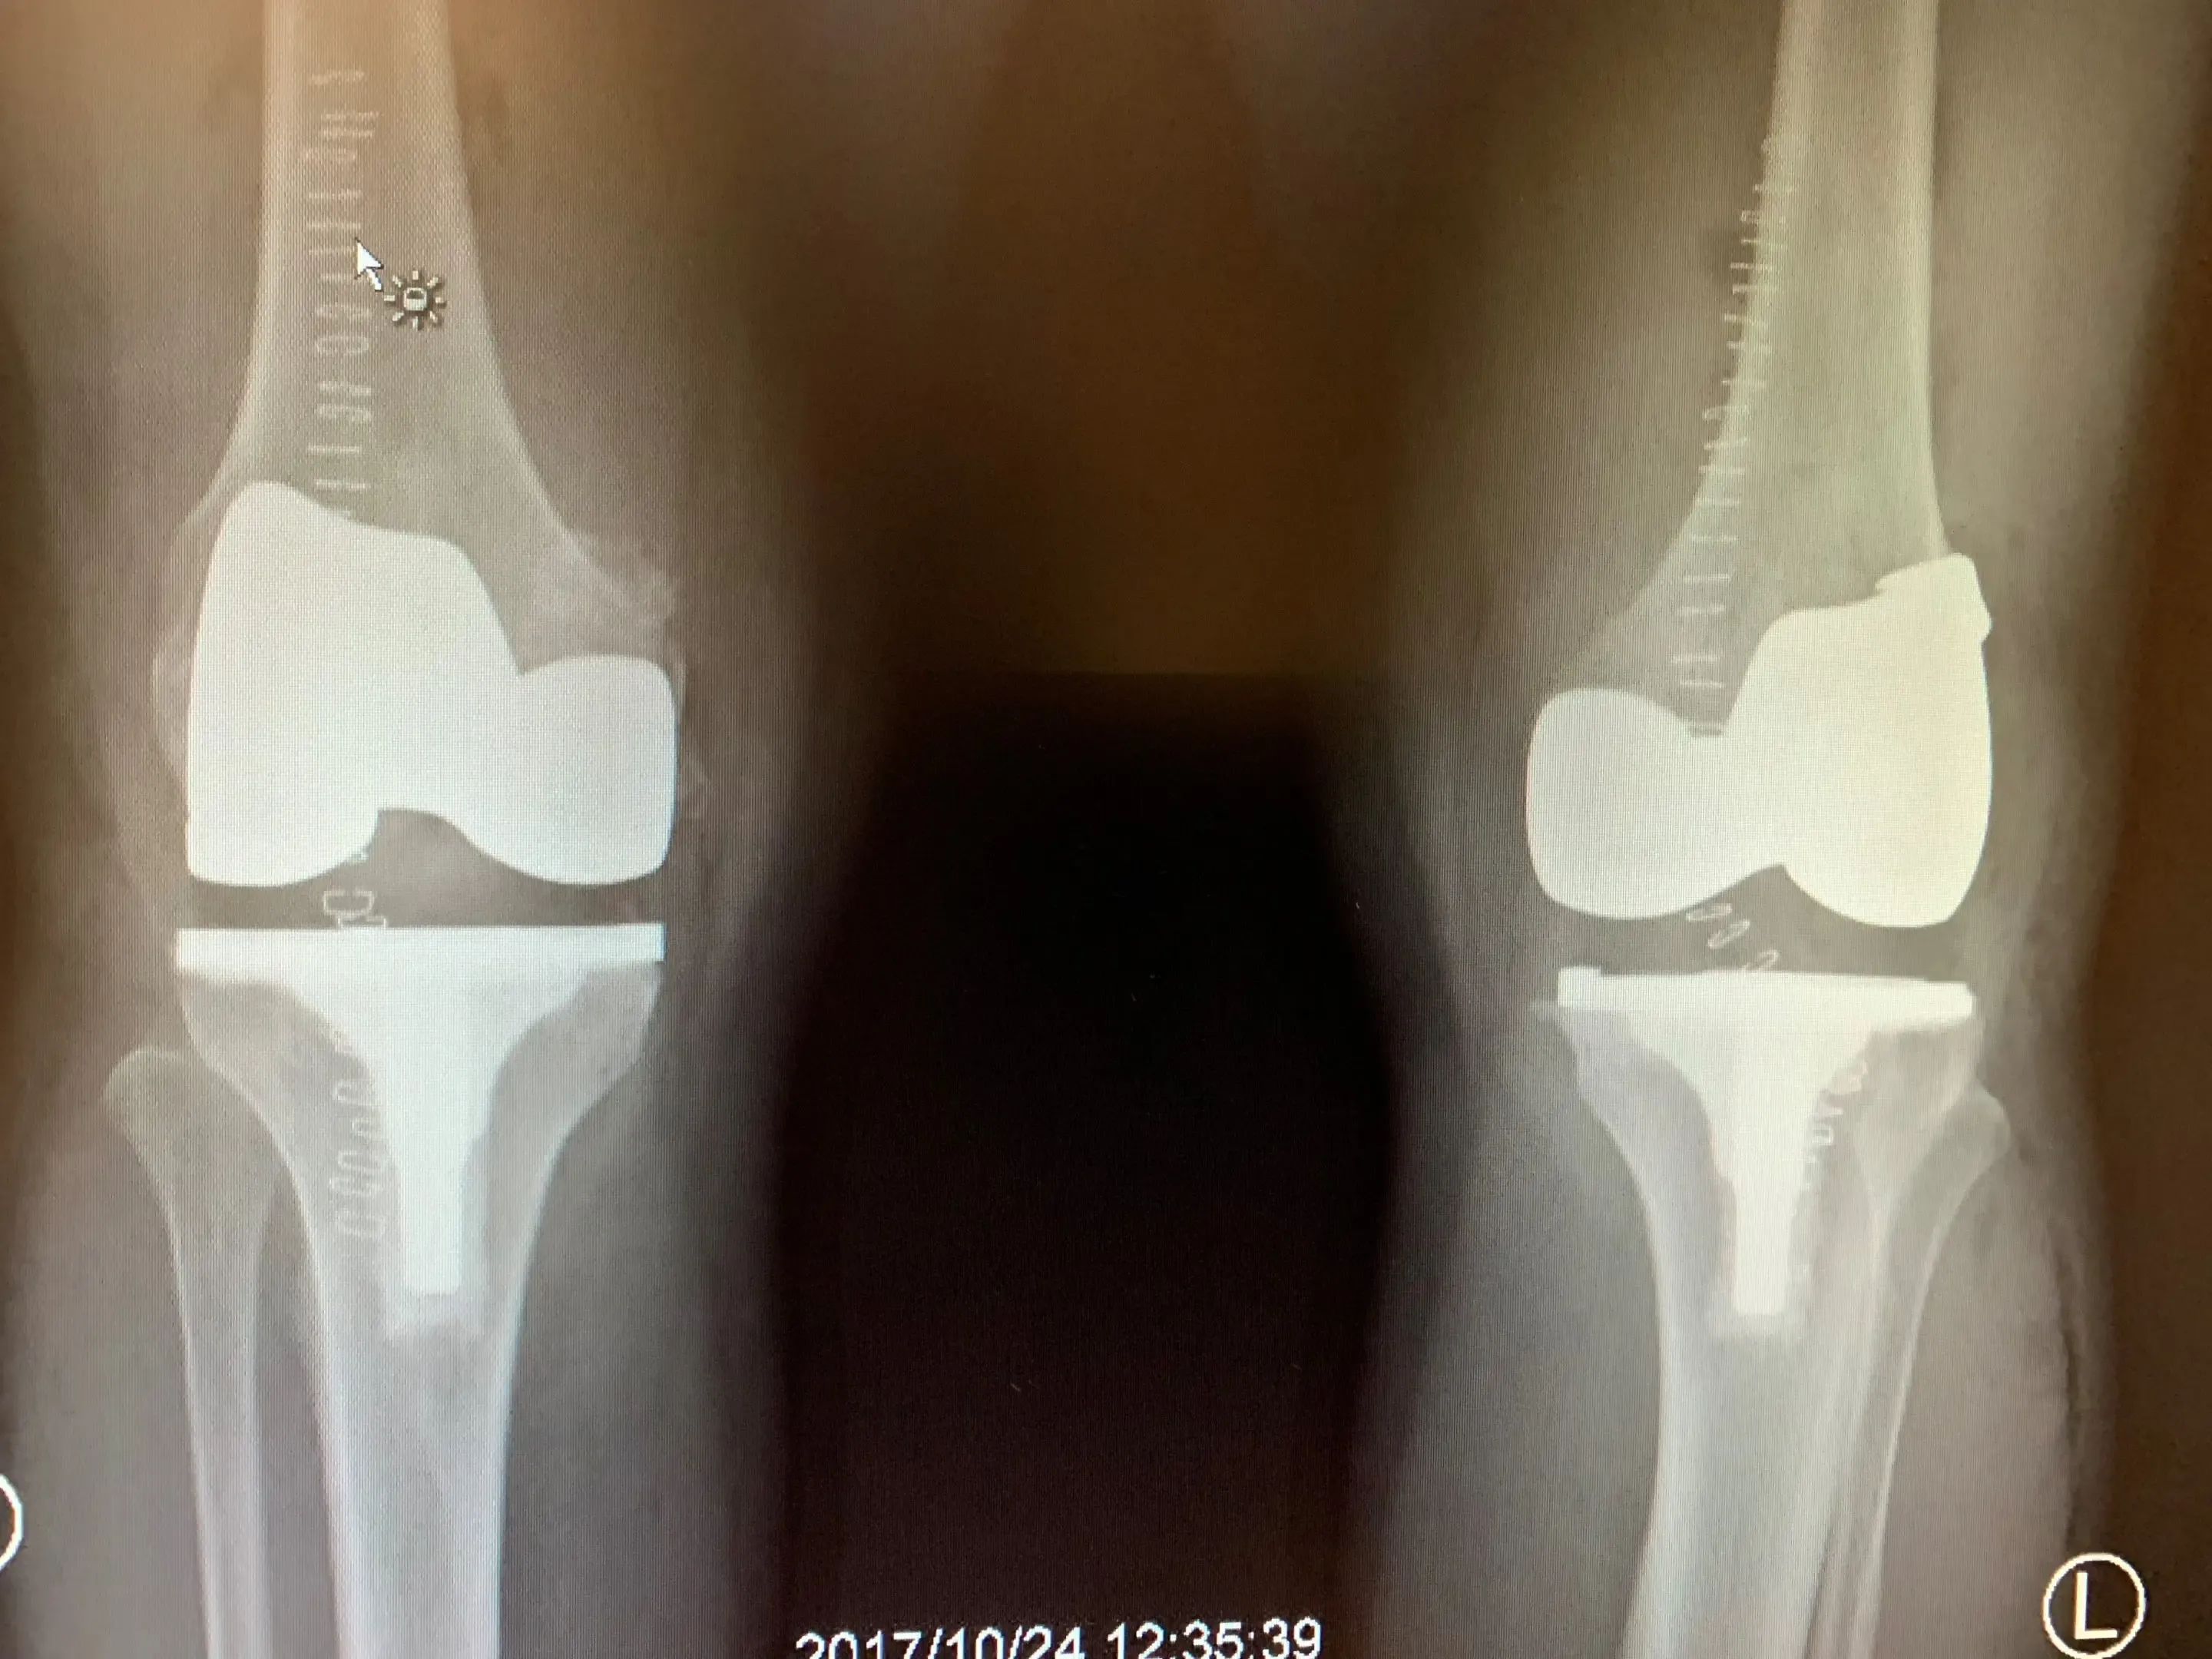

Post-op

Simultaneous bilateral knee replacement in a 54-year-old female.